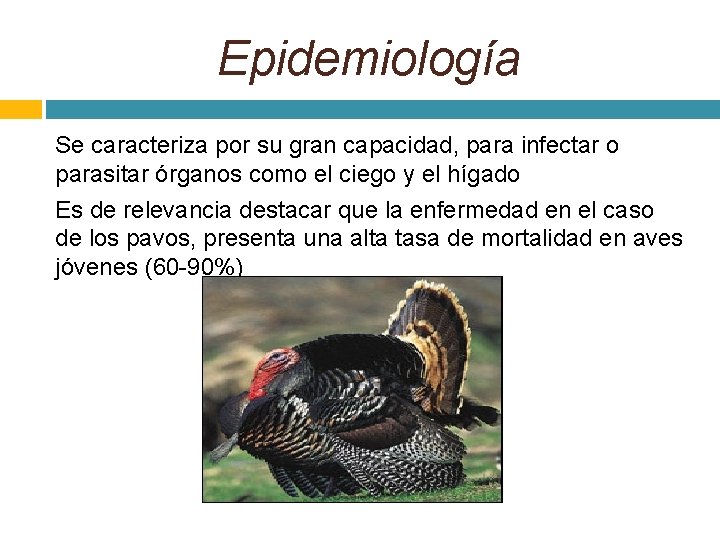

Epidemiología Se caracteriza por su gran capacidad, para infectar o parasitar órganos como el ciego y el hígado Es de relevancia destacar que la enfermedad en el caso de los pavos, presenta una alta tasa de mortalidad en aves jóvenes (60 -90%)